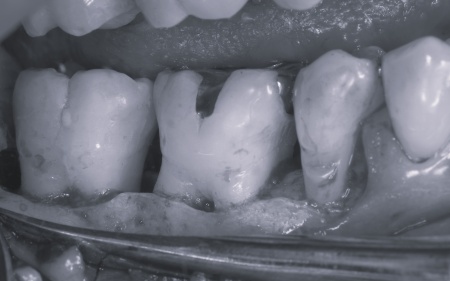

続いて上下左右の奥歯に対して、失われた歯を支える骨や歯根膜(歯を支える薄い膜)を再生させるため、骨の再生を促す材料などを充填する歯周組織再生療法を実施しました。

歯周組織再生療法を行いました。

下顎隆起を除去しました。